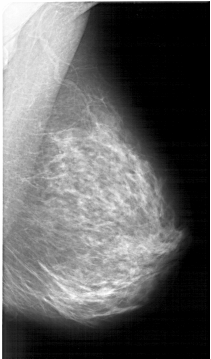

A_1259_1.RIGHT_CC

RIGHT_MLO LINES 5731 PIXELS_PER_LINE 3361 BITS_PER_PIXEL 12 RESOLUTION 43.5 NON_OVERLAY